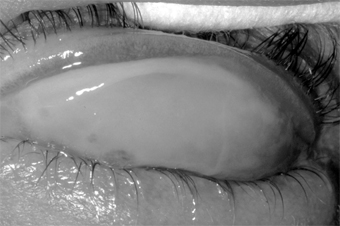

1. Hyperacute (and subacute) bacterial conjunctivitis-Purulent conjunctivitis-

(caused by N gonorrhoeae, Neisseria kochii, and N meningitidis) is marked by a profuse purulent exudate (Figure 5-1). Meningococcal conjunctivitis may occasionally be seen in children. Any severe, profusely exudative conjunctivitis demands immediate laboratory investigation and immediate treatment. If there is any delay, there may be severe corneal damage or loss of the eye, or the conjunctiva could become the portal of entry for either N gonorrhoeae or N meningitidis, leading to septicemia or meningitis.

Figure 5-1

Figure 5-1: Gonococcal conjunctivitis. Profuse purulent exudate. (Courtesy of L Schwab.)